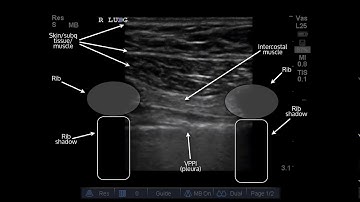

Pneumothorax: Ultrasound Image Interpretation